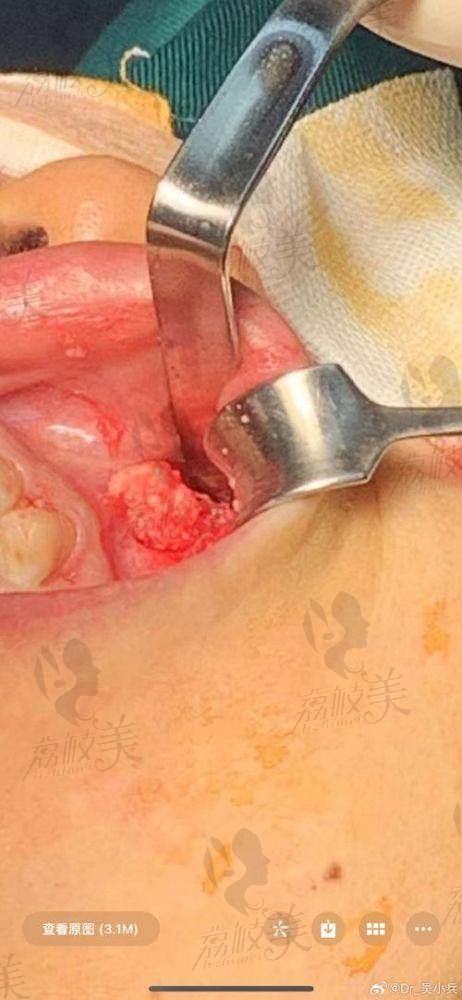

特别多求美者在小机构注射后,因成分不明发生硬结、红肿,甚至神经压迫,后悔莫及。但真正的问题不是“打过”,而是“能否安心取出”。生长因子一旦在皮下形成肉芽增生,随便处理风险极高。只有选择八大处郭鑫这样经验多的医生团队,才能做到精细定位、完全干净不复发。

相比玻尿酸,生长因子是强刺激活性物质,打入皮下可能引发肉芽、增殖、炎症反应、甚至脂肪坏死。取出过程若不精细,特别容易出现面部塌陷、二次感染或神经损伤。

而郭鑫在这方面操作稳、术前评估精细,能够配合高精度影像检查,分层取出,无需大面积翻皮剥离。术中注射特种降解酶,局部代谢加速,用专精手术器具柔性吸附残余异物,减少遗留。